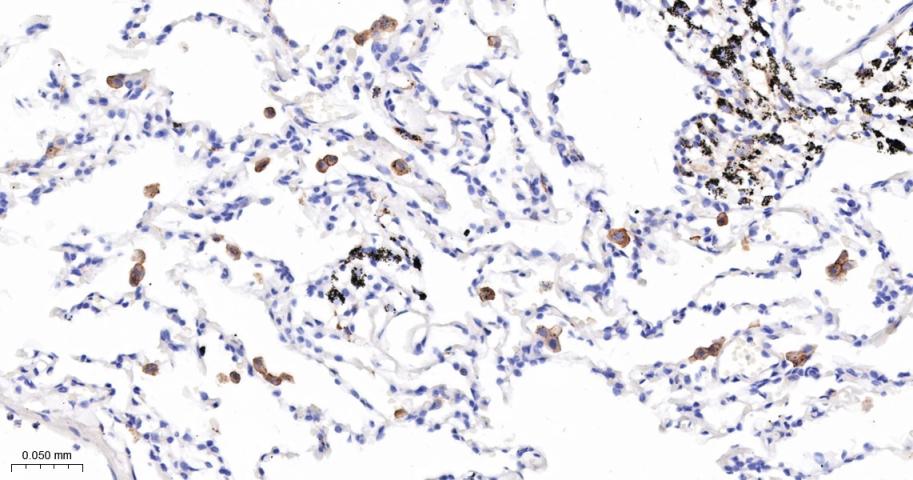

Paraformaldehyde-fixed, paraffin embedded Human Lung; Antigen retrieval by boiling in sodium citrate buffer (pH6.0) for 15 min; The section was incubated with CD163 Monoclonal Antibody, Unconjugated (bsm-43679M) at 1:200 overnight at 4°C, followed by conjugation to the bs-40296G-HRP and DAB (C-0010) staining.